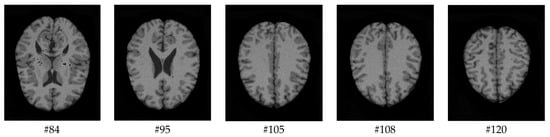

As mentioned before, the images of the first five datasets in Table 3 were used to evaluate the performance of the HMRF-WOA. Figure 1, Figure 2, Figure 3, Figure 4 and Figure 5 show some slices of a T1-weighted image (slices: 84, 95, 105, 108, 120). These brain images correspond to the slices under different types of conditions, such as database type, dimension image, noise level, intensity non-uniformity level, and slice thickness (mm). In Table 1, rows 1 to 5 summarize the parameters of Figure 1, Figure 2, Figure 3, Figure 4 and Figure 5, respectively. Figure 6 represents the ground truth segmentation of slices 84, 95, 105, 108, and 120. In this figure, each column contains the three tissues, GM, WM, and CSF, of each slice. Figure 7, Figure 8, Figure 9, Figure 10 and Figure 11 show the segmentation results, where the four tissues (BG, GM, WM, and CSF) are shown with different colors. The yellow, red, and green colors represent the segmented regions of GM, WM, and CSF, respectively. As we can also see from these figures, the resulting segmented images in Figure 7, Figure 8, Figure 9, Figure 10 and Figure 11 are almost close to the initial images in Figure 1, Figure 2, Figure 3, Figure 4 and Figure 5.

Figure 1. Slices with Noise = 0%, INU = 0% of database 1.

Computers 13 00124 g001